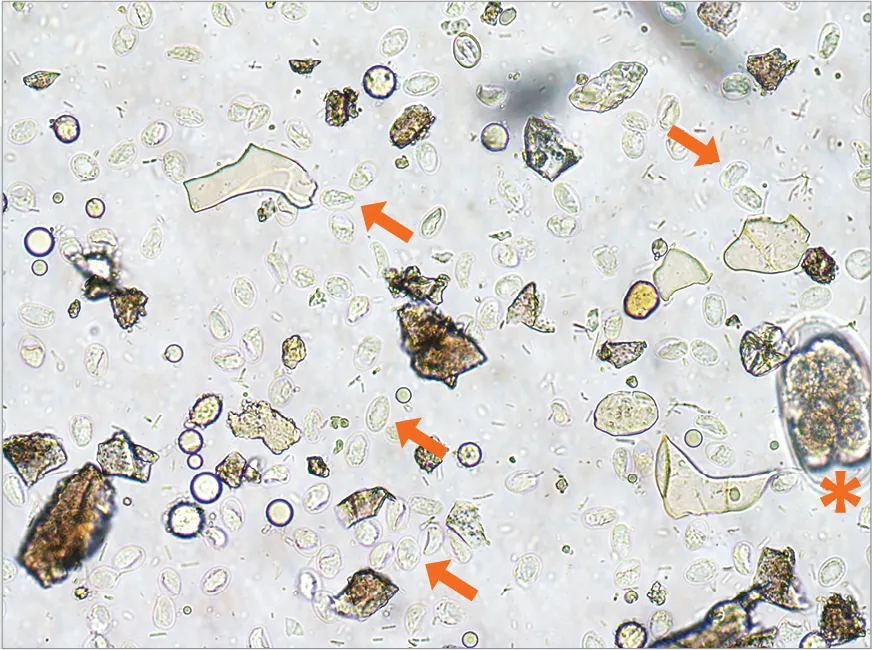

Giardia duodenalis cysts (arrows) recovered via centrifugal fecal flotation with zinc sulfate; hookworm egg (asterisk) for scale.

Once ingested, cysts reach the small intestine, where they excyst into trophozoites—the active, pathogenic form. Trophozoites multiply via binary fission, attach to the intestinal mucosa using a ventral disc, and disrupt nutrient absorption, leading to malabsorption and fatty stools (steatorrhea). As they travel toward the colon, trophozoites encyst and are shed intermittently in feces. The prepatent period in cats is 5 to 16 days, with cyclic shedding making detection challenging. Trophozoites rarely survive outside the host, unlike resilient cysts.

No single test detects all Giardia infections, so the Companion Animal Parasite Council (CAPC) recommends a multi-pronged approach for symptomatic cats: a direct fecal smear, centrifugal fecal flotation, and a vet-approved point-of-care antigen test. This combination boosts sensitivity, as cysts are tiny (10-12 µm), transparent, fragile, and shed intermittently.

Microscopy challenges include distinguishing Giardia from debris or yeasts, while human antigen tests lack validation for pets. Molecular PCR tests at reference labs offer high accuracy but higher cost and no routine genotyping for assemblages (A-H, with F most common in cats). For follow-up post-treatment, retest with flotation within 24-48 hours if diarrhea persists, to differentiate reinfection from resistance—critical given the short 5-day prepatent period.